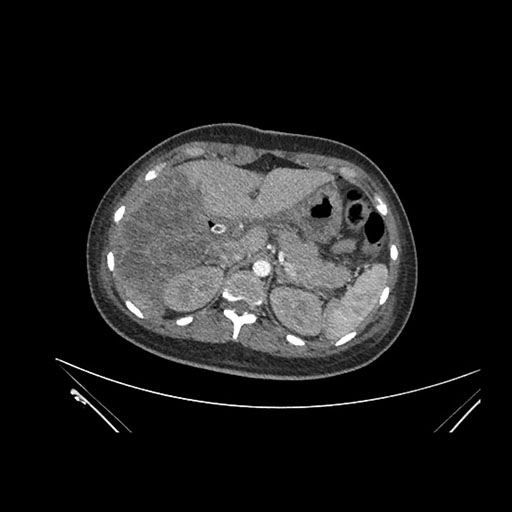

Axial Arterial

Axial Venous